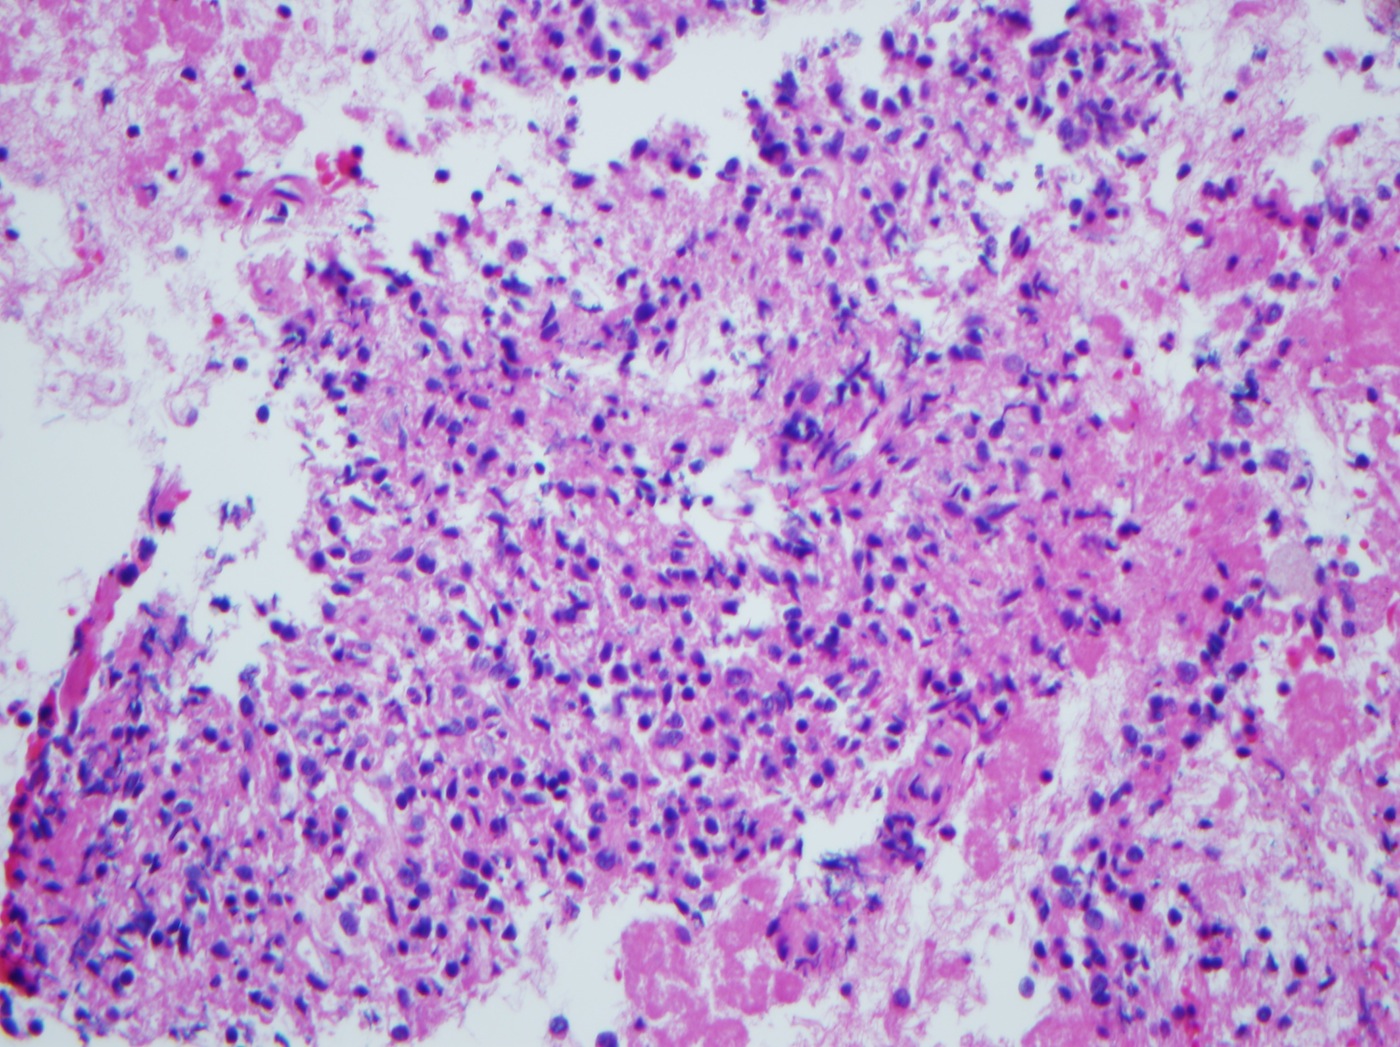

Pathology Outlines Accessory Accessory Tragus Pathology Outlines Accessory tragus is a relatively common congenital anomaly seen in ∼3 to 6 per 1000 live births. An accessory tragus (at) is a benign congenital malformation caused by an aberration. Histological features of accessory tragus include a thin layer of stratum corneum with a rugated epidermis, presence of eccrine glands, and irregular spatial positioning of vellus hair follicles. Also has. Accessory Tragus Pathology Outlines.

From www.pathologyoutlines.com